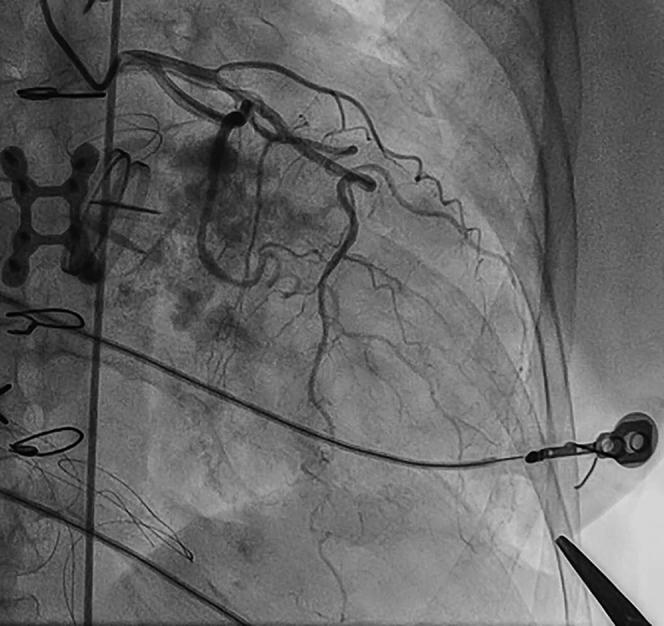

Thoracic endovascular aortic repair (TEVAR) provides an alternative to open surgery for a variety of aortic diseases. However, complex anatomy and previous operations may preclude traditional approaches to TEVAR. Percutaneous transapical access through the left ventricle is a feasible option to facilitate externalized "rail" wire support for complex TEVAR. We present the case of TEVAR for a residual type B aortic dissection facilitated by percutaneous transapical access.